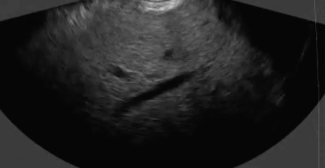

This educational session explores the latest innovations and practical strategies in endoscopic ultrasound (EUS), focusing on both diagnostic and therapeutic applications.

Participants will gain insights into optimizing fine-needle biopsy (FNB) techniques to enhance diagnostic yield, illustrated through expert-led presentations and real clinical cases.

Live Case: FNB Clinical Case